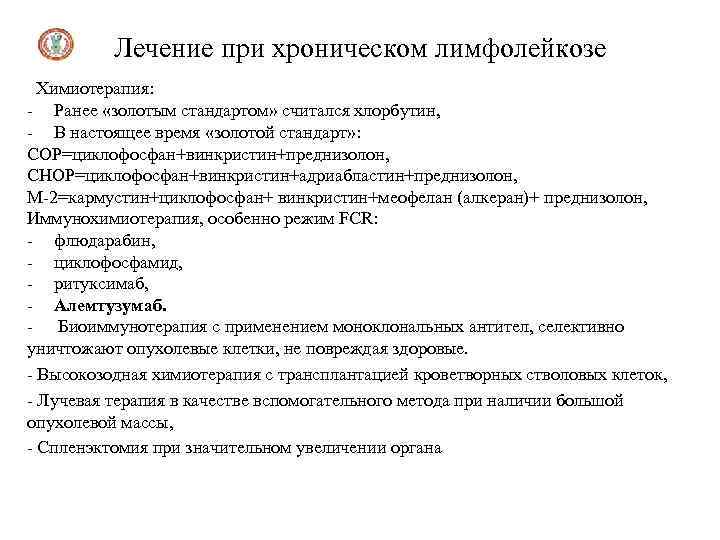

Лечение при хроническом лимфолейкозе Химиотерапия: - Ранее «золотым стандартом» считался хлорбутин, - В настоящее время «золотой стандарт» : СОР=циклофосфан+винкристин+преднизолон, СНОР=циклофосфан+винкристин+адриабластин+преднизолон, М-2=кармустин+циклофосфан+ винкристин+меофелан (алкеран)+ преднизолон, Иммунохимиотерапия, особенно режим FCR: - флюдарабин, - циклофосфамид, - ритуксимаб, - Алемтузумаб. - Биоиммунотерапия с применением моноклональных антител, селективно уничтожают опухолевые клетки, не повреждая здоровые. - Высокозодная химиотерапия с трансплантацией кроветворных стволовых клеток, - Лучевая терапия в качестве вспомогательного метода при наличии большой опухолевой массы, - Спленэктомия при значительном увеличении органа